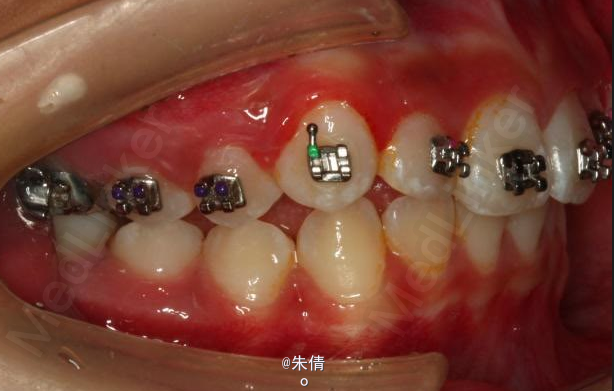

对于面型较好,拥挤度不大的病例,推磨牙向后不失为一种很好的方法,当然现在推磨牙后向的手段和方法很多,但是主要 是适应证的问题。我认为我们在做推磨牙向后,首先是考虑拥挤度,第二个要考虑的是现有的面型,第三点也是很重要的一点,是考虑牙弓后段拥挤度,Tweed-Merryfireld拥挤度的诊断方法将牙弓拥挤度分析分为三段,牙弓前段拥挤度,牙弓中段的拥挤度,以及牙弓后段的拥挤度。不管用什么方法或是手段推磨牙向后,一定不能将牙弓前端矛盾移到牙弓中段或是后段。今天给大家看一直面型,拥挤度不是很大推磨牙向后的病例。希望对大家能有所帮助。